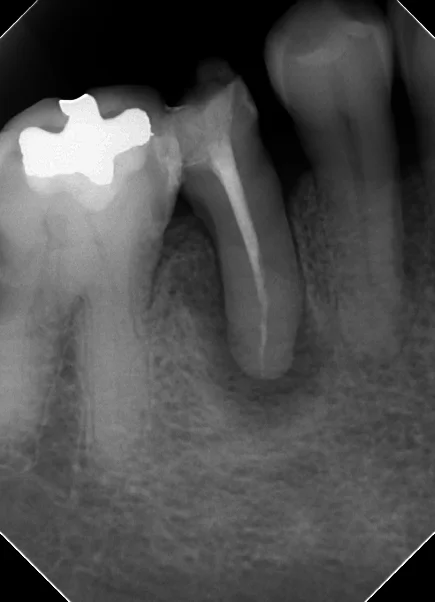

詰め終わった直後のレントゲンがこちらです。

根の先の方までしっかりと綺麗に詰まっています。

根の先の膿の部分は処置スタートから1ヵ月しか経過していない為、全く変化がない状態です。